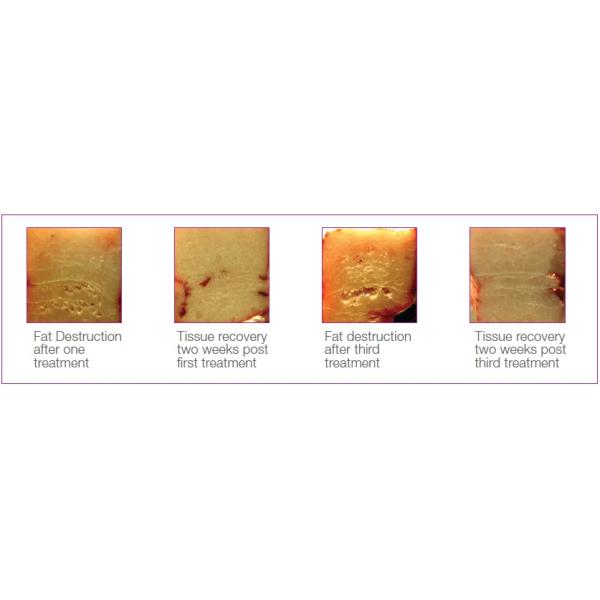

The HIFUSHAPE System is the first and only FDA cleared, non-invasive body shaping device that uses pulsed, focused ultrasound to mechanically (non-thermally) and selectively destroy fat cells at a designated focal point in the subcutaneous fat tissue without harming the skin, blood vessels, nerves or connective tissue, demonstrating measurable results in as little as 2 weeks.

Focused:Ultrasound energy is designed to precisely converge into a confined focal volume, targeting onlysubcutaneous fat at a controlled depth.

Pulsed:Energy is delivered in bursts resulting in a mechanical non-thermal effect that only targets tissue most susceptible to mechanical disruption keeping nerves, vessels and muscles safe and intact.